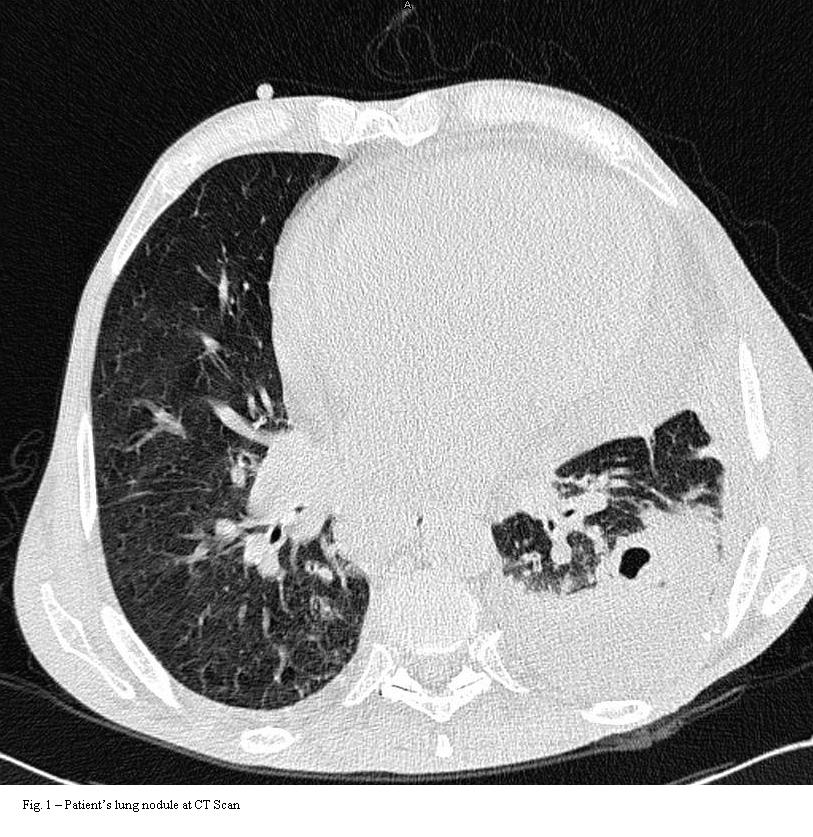

Brief tale of a bacteraemia by Rhodococcus equi with concomitant lung mass: what came first, the chicken or the egg?